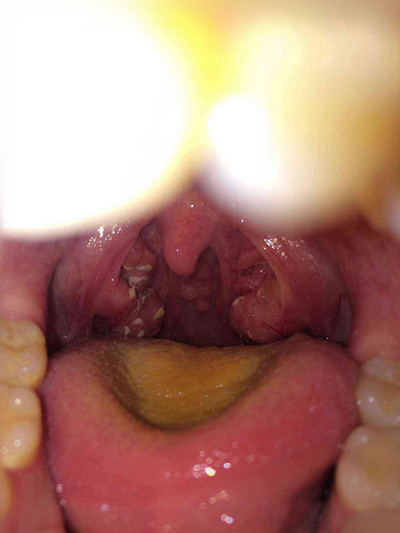

扁桃體週膿腫圖片